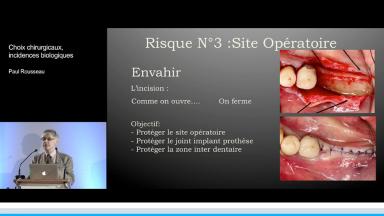

La présentation du Dr Rousseau reprend les choix auxquels est confronté le chirurgien-dentiste lors de la mise en place d’un implant dentaire.

De l’incision jusqu’aux sutures, le praticien fait face à une multitude d’options thérapeutiques qui conditionne la survie voire le succès de l’implant. La plupart des choix chirurgicaux repose sur la bonne compréhension des mécanismes biologiques de la cicatrisation et de l’homéostasie. Comprendre ces mécanismes, c’est orienter ses choix chirurgicaux vers un exercice raisonné de l’implantologie et accroître ses chances de succès.